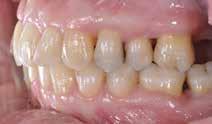

Der ses anterior trangstilling i begge kæber og overerupterede 1+1 og 2,1-1,2, hvilket resulterer i dybt bid med 2- tæt på ganepåbidning. Der er normale sidetandsrelationer, men der ses 5 mm horisontalt overbid (HOB) og 7 mm vertikalt

overbid (VOB). Papillen mellem 1+1 er betydeligt reduceret pga. fæstetab, og de mesialt kippede 1+1 har resulteret i en ”dark triangle”. Den facioorale funktion er for nuværende i.a. Panoramarøntgen (Fig. 1, I) viser marginalt knogletab i begge kæber og fravær af 8,7+7,8 og 8,7-8.

Objektivt anbefales behandling af det dybe bid, som ubehandlet forventes at forværres yderligere over tid. Patienten har ønske om behandling med æstetisk ortodontisk apparatur, alignere, og det vurderes muligt at behandle malokklusionen med alignere. Dog anbefales det generelt, at alignere undgås eller benyttes med væsentlige modifikationer af alignerens retention ved tandmobilitet, da dette ellers kan medføre jiggling, når aligneren tages af og på mange gange dagligt. På den anden side er der nogen evidens for, at alignerbehandling er associeret med bedre renhold og parodontal sundhed sammenlignet med fast apparatur (16).

Der planlægges alignerbehandling af begge kæber med intrusion af 1+1 og 2,1-1,2, nivellering af trangstilling UK med interproksimal reduktion (IPR) (Fig. 2 A, B) og senere IPR OK for reduktion af dark triangles mellem incisiverne efter nivellering. Patienten instrueres i at benytte alignere 20-22 timer/ dag med alignerskift hver 7. dag, og patienten ses hver 3.-8. uge under forløbet. Den første alignerserie består af 16 alignere for nivellering OK/UK og IPR i UK (Fig. 2). Efter denne serie planlægges IPR mellem incisiverne i OK for reduktion af dark triangles (Fig. 3) samt yderligere intrusion af OK og UK-fronten i 12 refinement-alignere. Patienten udviser god kooperation og er meget tilfreds med alignerapparaturet, som er mindre synligt end det faste apparatur (Fig. 4).